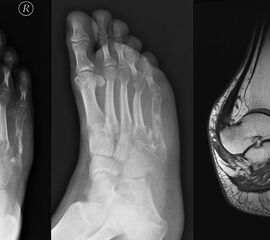

Enchondrom

Das Enchondrom ist der häufigste Knochentumor im Bereich von Hand und Fuß und nach dem Osteochondrom der zweithäufigste gutartige Knochentumor überhaupt. Die geschlechtliche Verteilung ist ausgeglichen, Enchondrome finden sich meist bei Patienten zwischen 20-40 Jahren. Dieser chondrogene Tumor verhält sich meist asymptomatisch, kann aber durch eine Knochenexpansion und Schwellung sowie Spontanfrakturen (Abb. 17) auffallen. Radiologisch zeigen sich in der Regel gut abgrenzbare Osteolysen, Matrixverkalkungen sind typisch aber nicht obligat. Die MRT zeigt typischerweise eine annähernd flüssigkeitsäquivalente Signal­qualität mit niedrigen Signalintensitäten in T1 und hoher Signalgebung in T2, die Binnen­struktur weist eine für chondrogene Tumoren typische Lobulierung mit KM-Aufnahme auf.

Im Gegensatz zu Osteochondromen ist die Lage von Enchondromen nicht auf die Metaphyse beschränkt. Sie finden sich auch im Bereich der Epi- und Diaphysen. Die kurzen tubulären Knochen der Metatarsalia und Phalangen sind bevorzugt betroffen. Hier findet sich die Läsion typischerweise im Bereich der proximalen Phalangen oder distalen Metatarsalia, eine Ausbreitung auf die gesamte Diaphyse ist von hier aus jedoch nicht ungewöhnlich. Die Möglichkeit einer malignen Entartung (Chondrosarkom) ist im Bereich der Metatarsalia und Phalangen im Vergleich zu den langen Röhrenknochen und platten Knochen extrem selten 33. Die übliche Therapie besteht in einer gründlichen Curettage. Je nach Größe des Defekts und Schwächung der Kortikalis kann die Transplantation eines stabilisierenden kortiko­spongiösen Spans notwendig werden. Zusätzliche osteosynthetische Verfahren sind nur selten erforderlich.